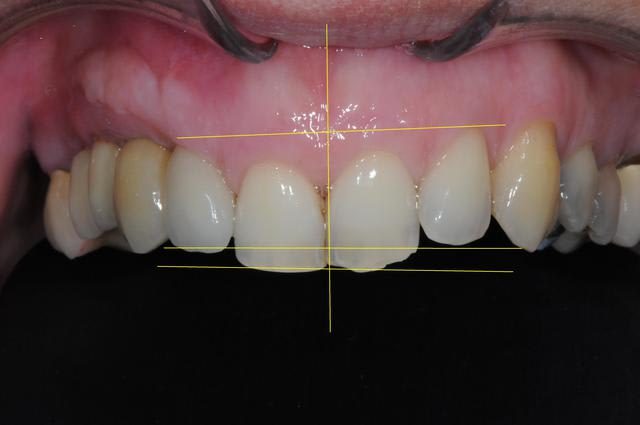

mise à jour et aménagement tissulaire type Palacci

modification des collets et des bords libres

prise empreinte

piliers

couronnes...